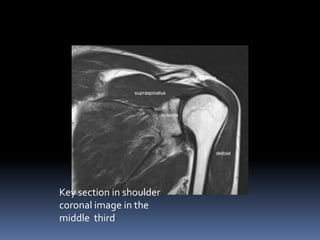

Key section in shoulder

coronal image in the

middle third